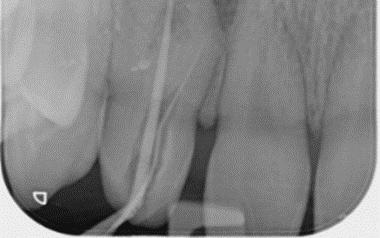

Dens Invaginatus (DI), a relatively uncommon developmental dental anomaly characterized by the invagination of enamel and dentin into the tooth structure, particularly the Type III variant which extends beyond the cementoenamel junction and possesses its own independent apical foramen, presents intricate endodontic challenges stemming from its often highly complex and unpredictable internal anatomy. Successful management requires a meticulous and tailored approach. This case report details the successful non-surgical root canal treatment of a Type III DI in a 15-year-old male's maxillary lateral incisor (tooth 12) with a pulpless, infected root canal system and a chronic apical abscess attributed to the DI defect. Preoperative evaluation involved clinical examination and periapical radiographs. While cone-beam computed tomography (CBCT) offers detailed visualization of such anomalies, its use was avoided to minimize radiation in this young patient. Clinical findings and conventional radiographs were deemed sufficient for treatment planning.

The endodontic therapy was conducted over four appointments. Access cavities were precisely prepared for both the main canal and the invagination, guided by a dental operating microscope. Working lengths were determined electronically and confirmed radiographically. The main canal was shaped using rotary files. The narrow, irregular invagination was meticulously instrumented with hand files, utilizing both EDTAC and copious sodium hypochlorite irrigation for thorough cleaning and disinfection. Calcium hydroxide mixed with Ledermix was used as the initial intracanal medicament to address infection and inflammation.

The fourth appointment involved re-access, final EDTA irrigation, and obturation. The main canal was obturated with a single gutta-percha cone and AH-26 Cement. Due to the invagination's complex morphology, a thermoplasticized injectable gutta-percha system ensured complete three-dimensional filling of this aberrant space. The access cavity was then permanently restored with composite resin to prevent microleakage.

A six-month clinical and radiographic follow-up demonstrated a successful outcome. The patient was asymptomatic with no tenderness, and the previously present sinus tract had resolved. Radiographic evaluation revealed a significant reduction in the periapical radiolucency, indicating healing of the chronic apical abscess.

In conclusion, this case underscores the critical role of meticulous chemomechanical preparation of both the main and invaginated canal systems, the strategic use of appropriate intracanal medicaments, and the application of tailored obturation techniques, such as thermoplasticized gutta-percha for complex anatomies, in achieving successful endodontic outcomes in challenging DI cases. While CBCT is a valuable diagnostic tool, this case highlights that thorough clinical assessment combined with carefully interpreted conventional radiographs can be sufficient for diagnosis and treatment planning in younger patients. Ultimately, a strong foundation in basic endodontic principles and the ability to adapt treatment strategies to the unique anatomical complexities of Dens Invaginatus remain paramount for successful management.

X-ray 1: A large periapical radiolucency in association with tooth #12, with a gutta-percha point tracing through the visible sinus tract originating from this area.

X-Ray 5: The six-month follow-up radiograph demonstrates a significant decrease in the dimensions of the radiolucent area, consistent with a favourable outcome of the endodontic treatment.